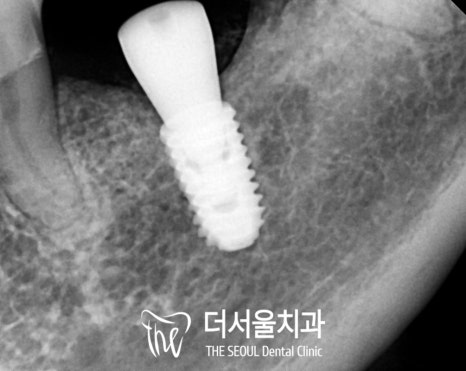

픽스처의 고정이 끝나고 나면

뼈와 단단하게 잘 붙었는지

고정력 측정기를 이용하여

수치를 확인합니다.

주변으로 하얗게 치조골이

잘 차올랐다면

맞춤형 어버트먼트 제작을 위한

본뜨기 과정과 잇몸 치유 단계를 거치고

최종 크라운을 올려드립니다.

골질의 상태에 따라

보철을 브릿지로 제작하여

저작력을 분배할 수 있도록 하였으며